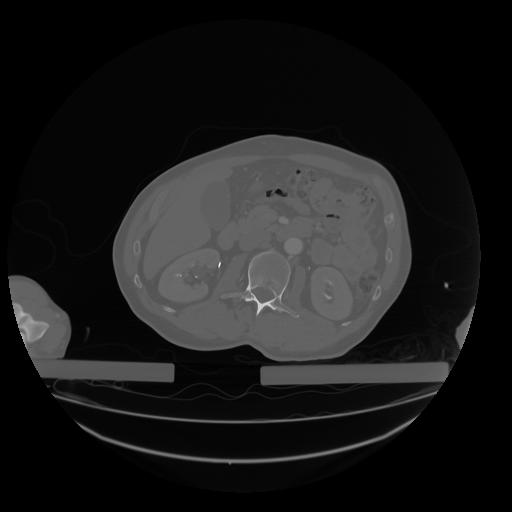

28 CUERPO,CE,Vol,2.0,CUERPO,,